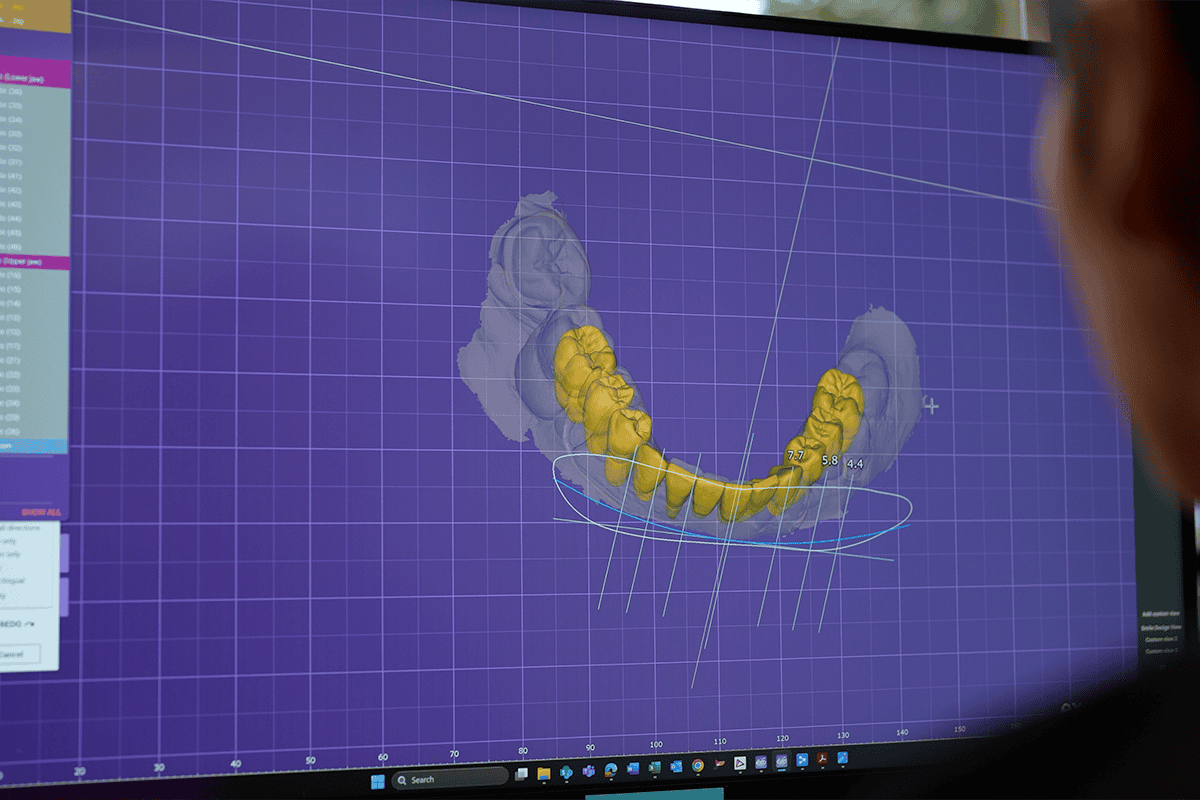

At Advanced Dental Artistry, we use detailed scans and thorough examinations to understand your teeth, gums, and bone structure. If needed, we address any underlying oral health issues first to help ensure a strong foundation before moving forward with implants.